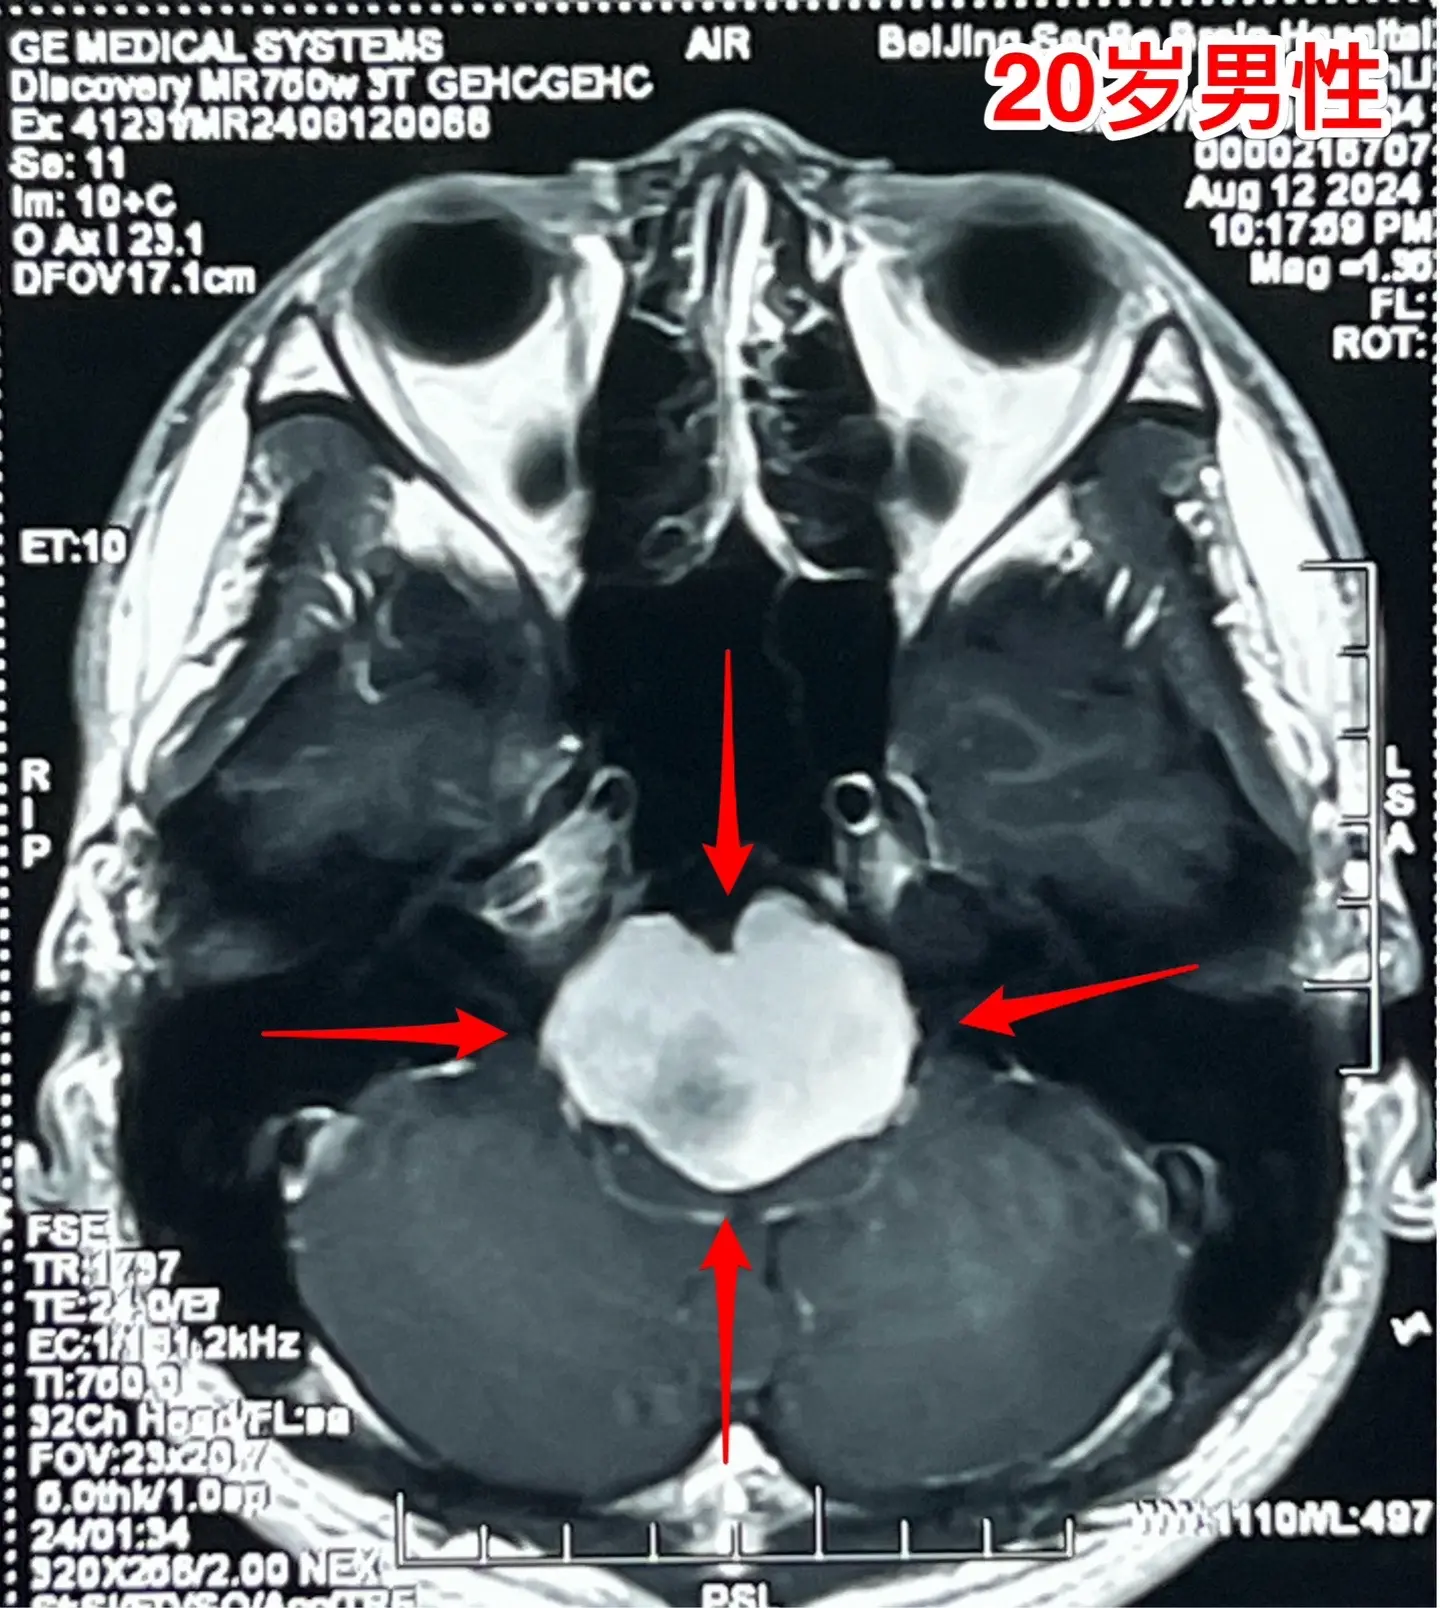

头晕、吞咽困难、行走不稳、大小便障碍。20岁漳州的小伙子,2个月前出现头晕,一个月前出现吞咽困难,半个月个月前出现多睡,一周前出现行走不稳、视物重影、发音不清晰,而且有大小便障碍。 一般人认为这些症状都是七八十岁的老人才会有的,怎么会出现在20岁的年轻人身上呢?他到底得了什么病? 磁共振和CT显示脑干腹侧有一个巨大囊肿,对脑干有明显的压迫,考虑为肠源性囊肿。针对这个病,只有选择作手术切除囊肿,病人的症状才有希望好转。 2024.8.14作了手术,术中看见囊壁与脑干的神经、基底动脉的分支血管粘连。切除大部分囊壁,清除了囊内容物,脑干得到充分减压。 手术后病人的症状显著改善了!